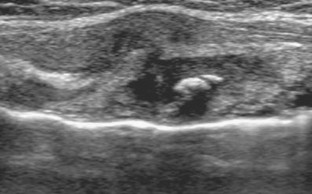

A 17-month-old boy presented with a palpable anterior chest wall mass and was evaluated by chest radiography, sonography, and MRI. No history of trauma was provided initially. Sonography and MRI showed a costal cartilage fracture with overlying hematoma. Identification of a fracture isolated to the costal cartilage is rare and this is a unique case among children. In the appropriate clinical setting, costal cartilage fractures can be confirmed by sonography alone, and follow-up assessment can be based on clinical evaluation without the need for additional cross-sectional imaging.

Fig. 1